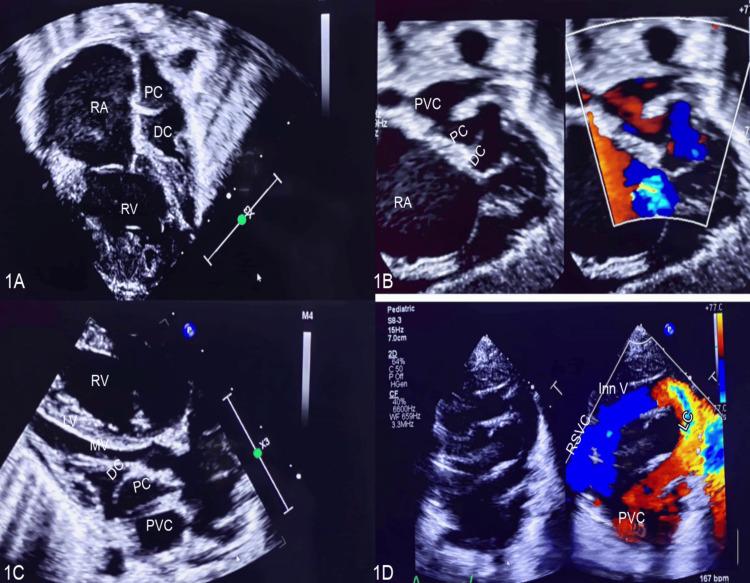

Levoatriocardinal vein has rarely been described with cor triatriatum. We report a case of a newborn with respiratory distress who was found to have cor triatriatum sinister with a decompressing levoatriocardinal vein on transthoracic echocardiography. The pulmonary venous confluence received all pulmonary veins and drained to the proximal left atrial chamber through significant communication. Moreover, the cor triatriatum membrane separated the left atrial body into proximal and distal left atrial chambers with a restrictive opening in the membrane, causing severe flow limitation to the cardiac output, severe pulmonary arterial hypertension, and significant right ventricular dilatation. In addition, a sizeable levoatriocardinal vein decompressed the pulmonary venous confluence drained superiorly to the left innominate vein. She had a successful surgical repair by resectioning the cor triatriatum membrane and ligating the levoatriocardinal vein. The patient had improved pulmonary arterial pressures and right ventricular dimensions at the one-month follow-up. The case highlights the rare association of the levoatriocardinal vein and cor triatriatum, and its presence signifies severe obstruction at the level of cor triatriatum.